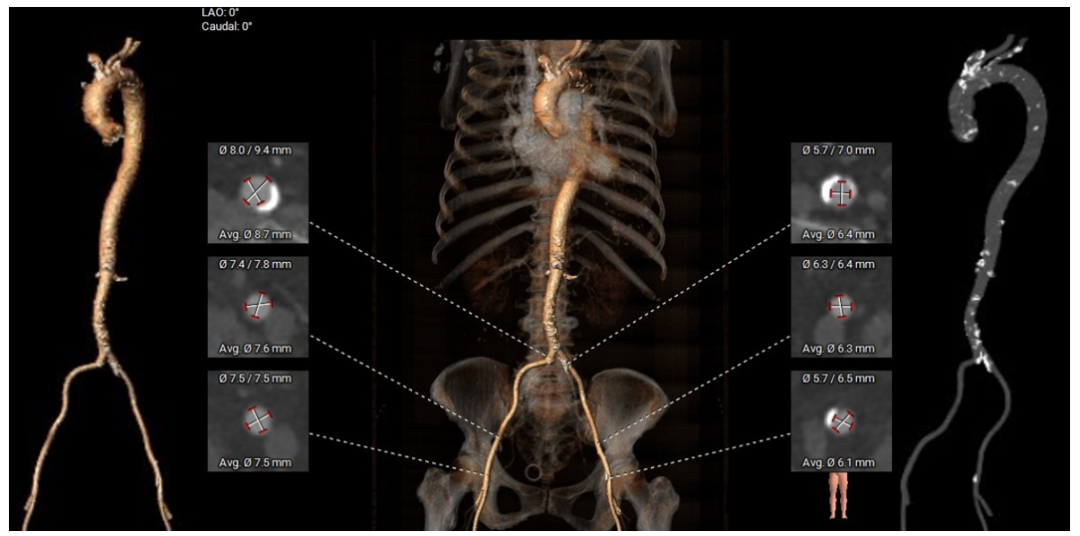

外周血管及主动脉弓解剖:

弓部及入路评估: